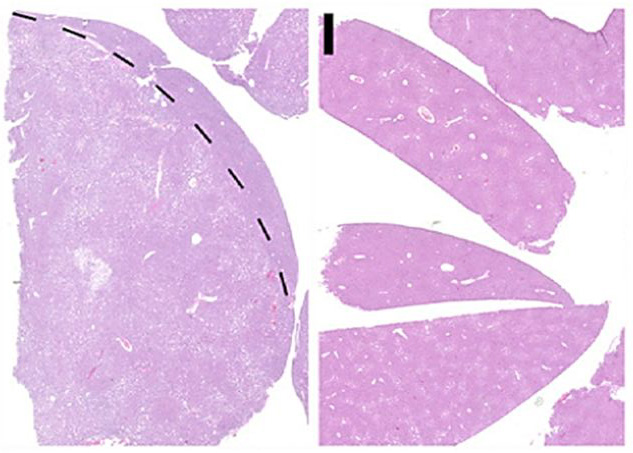

Both cancers are different regarding their behavior and are also treated differently. The microenvironment of cancer cells, and in particular, the special form of cell death occuring in this environment, proved to be decisive for the development of the respective type of cancer. The scientists showed that precursors of cancer cells in whose environment cells died by apoptosis, the classical cell death, developed into hepatocellular carcinoma. Precancerous cells, in whose environment cells died due to necroptosis, led to intrahepatic cholangiocellular carcinoma. In necroptosis, the cell membrane dissolves, and the cell content causes inflammation in the environment of the cancer cell, while in classical programmed cell death small vesicles are formed which are eliminated by the immune system.

The results could be verified both in mouse models and in human tissue samples. Cancer researcher Xin Wei Wang from the Laboratory of Human Carcinogenesis (Center for Cancer Research, National Cancer Institute, Bethesda, USA) contributed crucial human analysis data, and Oliver Bischof, a distinguished epigeneticists from the Institut Pasteur (Laboratory of Nuclear Organization and Oncogenesis) in Paris, unraveled how the microenvironment affects gene regulation in the cancer cell.